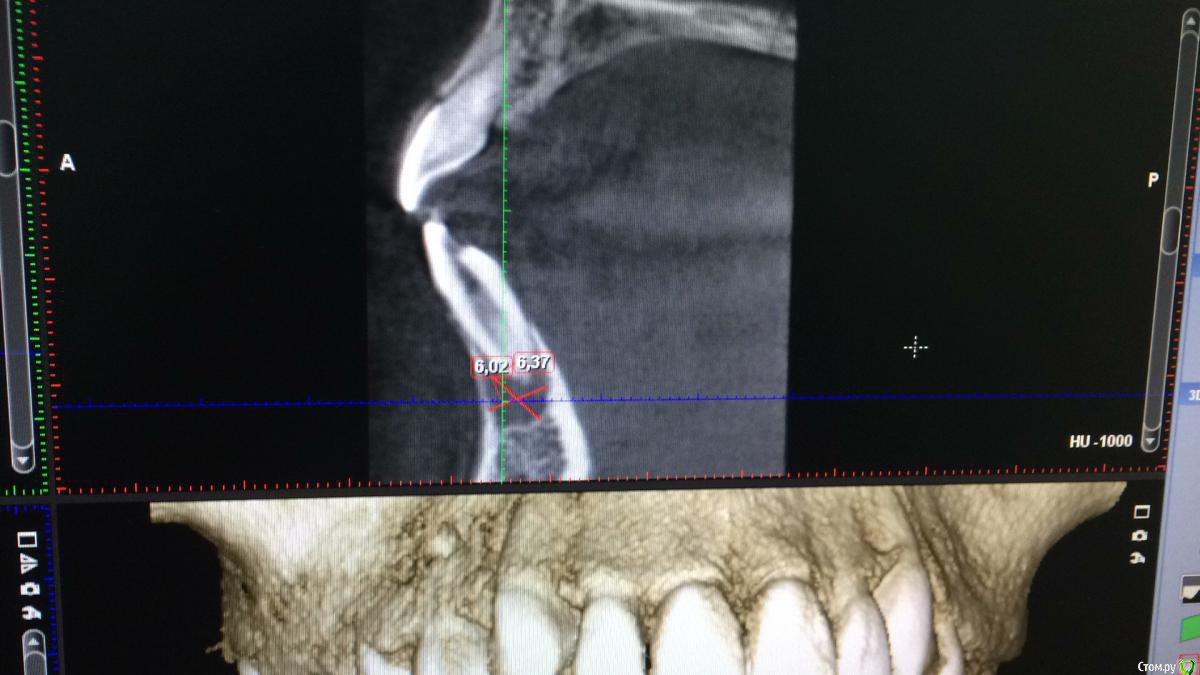

DenisV Опубликовано 16 февраля, 2017 Автор Поделиться Опубликовано 16 февраля, 2017 Коллеги кто что думает? Мальчик 12 лет обратился с жалобами на боль в зубе 4.1, зуб раскрыт, получен эксудат из канала.Зуб был ранее интактен в госке зуб открыли и назаначили полоскания, сейчас подвижность 2-3 степени. Мама отмечает ранее травму этого зуба. Ссылка на комментарий

Давлетшин Опубликовано 20 февраля, 2017 Поделиться Опубликовано 20 февраля, 2017 (изменено) Добавлю, что кажется, что канал раздваивается на середине корня, по фото плохо видно. Т.е. кальций в оба канала. и каналы очень хорошо мыть и УЗ. а по размеру разряжения не особо страшно.И что между 44 и 45? Изменено 20 февраля, 2017 пользователем Давлетшин Ссылка на комментарий